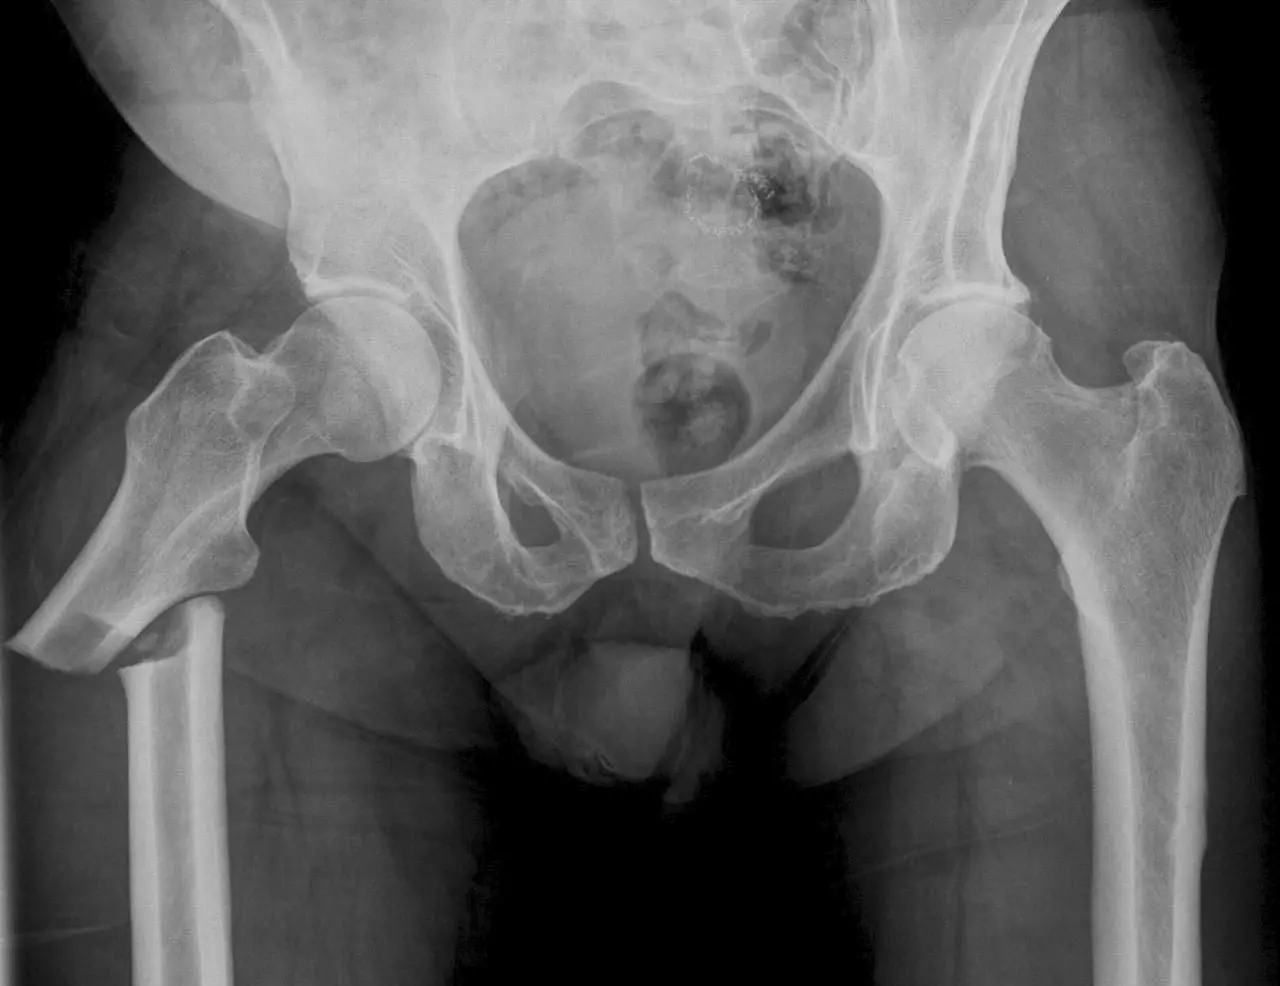

К группе таких заболеваний относят лейкозы, лейкемии и множественную миелому. Все эти заболевания характеризуются повреждением красного костного мозга, который выполняет кроветворную функцию. Зачастую злокачественные опухоля связанные с повреждением костного мозга обладают выраженным клеточным атипизмом, что негативно влияет на течение заболевания. Быстрый рост и сопутствующее повреждение костей вызывают выраженные боли в костях имеющих губчатую структуру строения, например в костях черепа, рёбрах и телах позвонков. Часто онкологические больные отмечают боль в тазовых костях.

- Боль над лобковой костью – может возникнуть в результате травмы одной из ветвей лобковой кости при переломах таза или же может ошибочно расцениваться, как боль в костях, однако будет связана с заболеваниями органов малого таза.

- Боль в бедренной кости может быть связана с травматическим повреждением в результате остеопороза, или сильного удара в область повреждённой нижней конечности. Боль в бедре также может возникнуть из-за онкологического процесса.